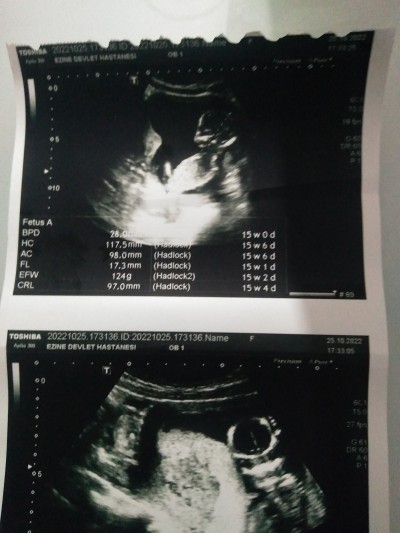

16+3 haftalık hamileyim daha cinsiyeti öğrenemedik:)

image